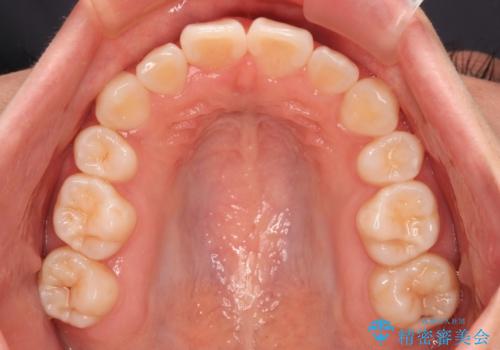

- 歯のデコボコや八重歯、クロスバイトを気にして来院された患者様です。

上下左右第一小臼歯4本を抜歯し、ワイヤー装置にて歯列を整え、さらには少しでも口元を引っ込めるよう矯正治療を行うこととしました。

上下の骨格での左右差が小さかったことと、抜歯矯正であったことで、上下正中の位置をきれいに合わせることができました。